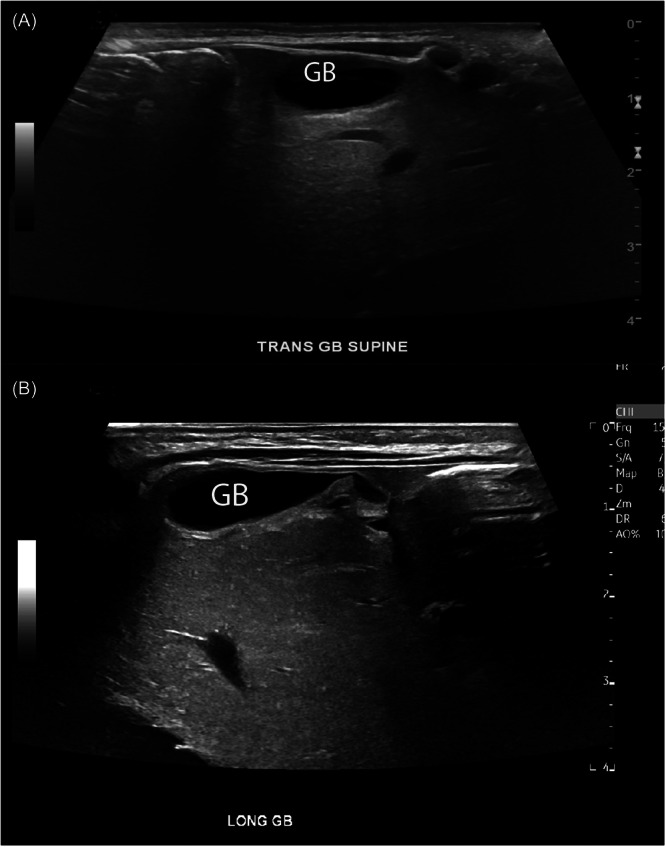

Congenital hepatic anomalies may be associated with important intestinal abnormalities, vascular anomalies, or may be asymptomatic and discovered incidentally. Uncommon and rare anatomic liver and biliary disorders include left-sided gallbladder, wandering liver, malrotation of the liver, and hepato-diaphragmatic interposition of the bowel (Chilaiditi syndrome). This report describes an infant with incidentally discovered malpositioning of the gallbladder to the superior surface of the left hepatic lobe, coupled with Chilaiditi syndrome, a configuration that has not been described in the literature. Management considerations are discussed.